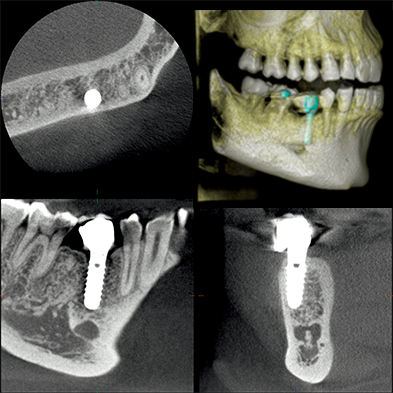

インプラントを顎の骨に入れる場合、顎の高さや厚み、神経までの距離などを正確に確認する必要があります。歯科用CTで正確に確認することで、インプラントの長さや太さが決まり、安全に顎に入れることが可能となります。

副鼻腔の状態、歯の根と副鼻腔の関係、神経やインプラントの関係など、いろいろな方向から観察できるため、治療の精度や安全性が向上し、患者様にこれまで以上の治療をご提供することが可能となりました。